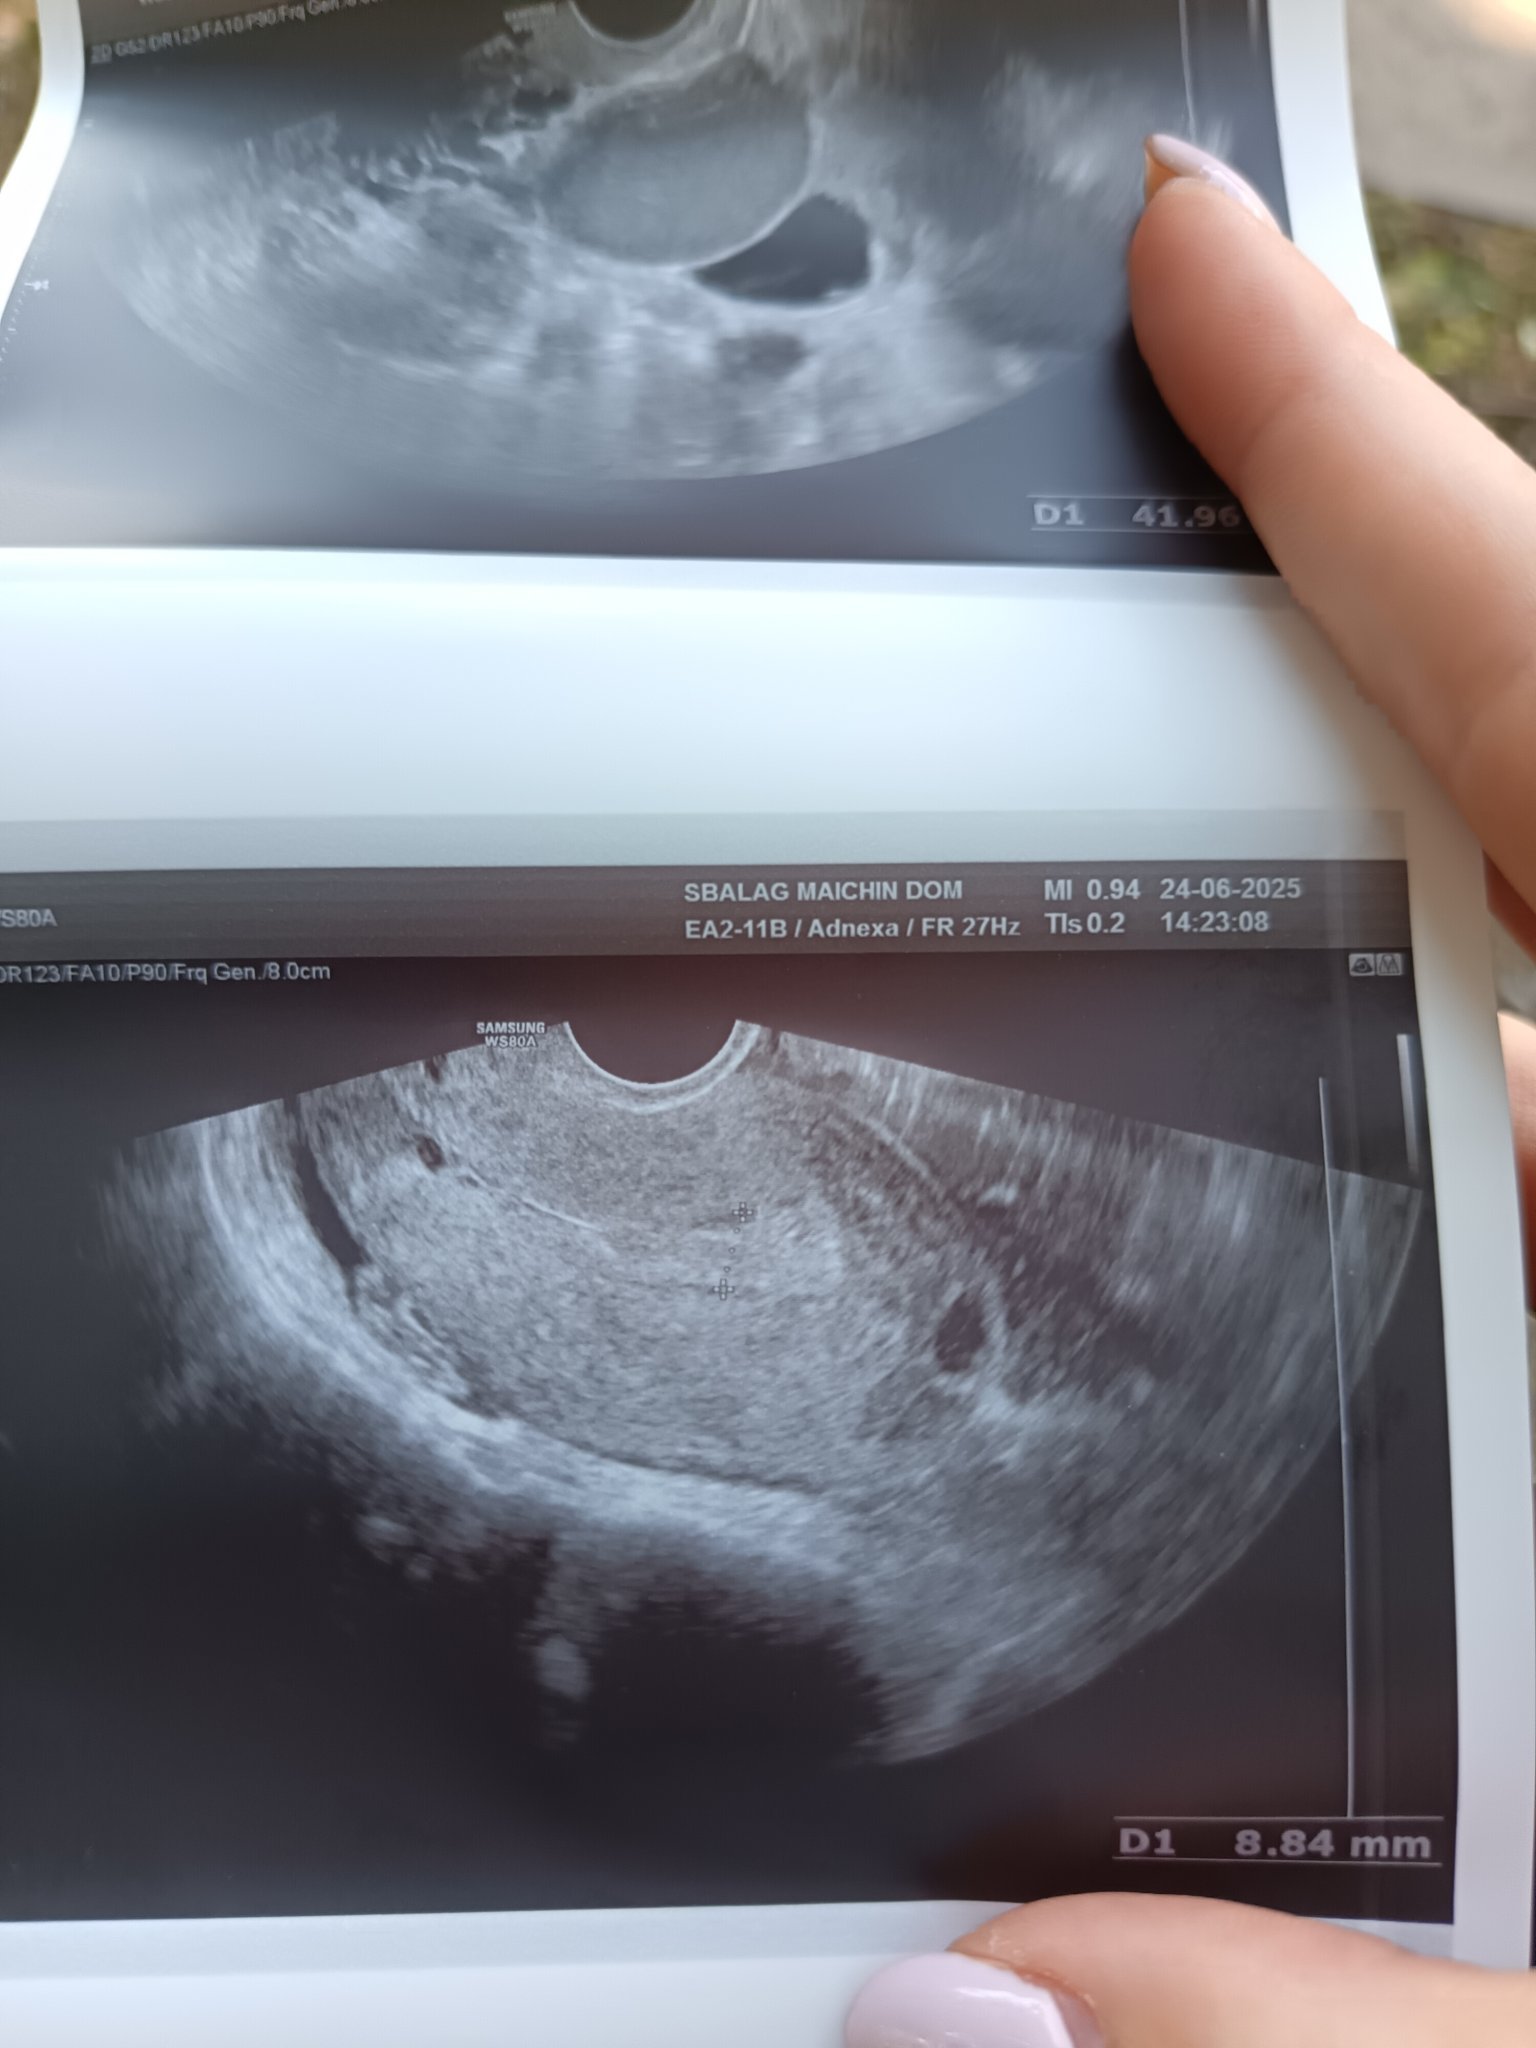

Какво представляват белите точки в плодния сак на ехографската снимка?

Какво представлява жълтото тяло на ехографската снимка?

Какво представляват черните точки в матката на ехографската снимка?

прикачвам тази снимка тук доктора каза че е кухо яйце според вас кухо яйце ли е ?